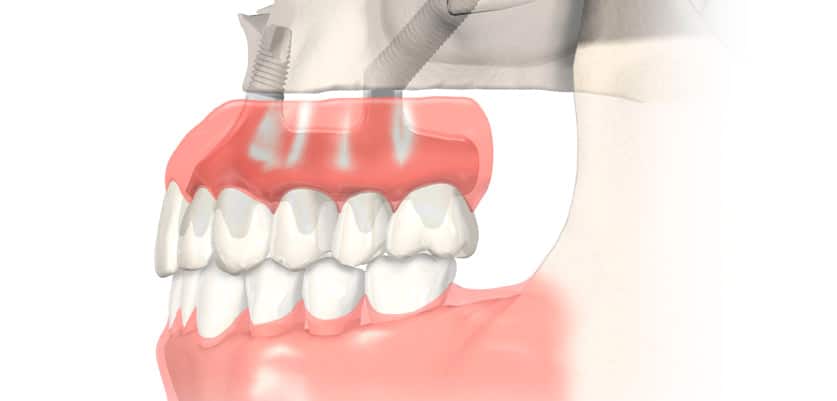

Los implantes cigomáticos son una solución avanzada en implantología dental diseñada para pacientes con una pérdida ósea severa en el maxilar superior. A diferencia de los implantes convencionales, estos implantes son más largos y están hechos de titanio para poder anclarse en el hueso cigomático, también conocido como hueso del pómulo o malar.

Este hueso, ubicado en la parte superior del rostro, ofrece una densidad y estabilidad excepcional, incluso en pacientes que han perdido todos sus dientes desde hace muchos años. Por ello, representa un punto de anclaje ideal para fijar los nuevos dientes sin necesidad de recurrir a injertos óseos.

En muchos casos, los implantes cigomáticos se combinan con 2 a 4 implantes convencionales más cortos colocados en la parte frontal del maxilar, siempre que haya suficiente hueso en esa zona. Y, sobre todos ellos se coloca una prótesis fija, devolviendo así la estética y función maxilar de forma inmediata al paciente.